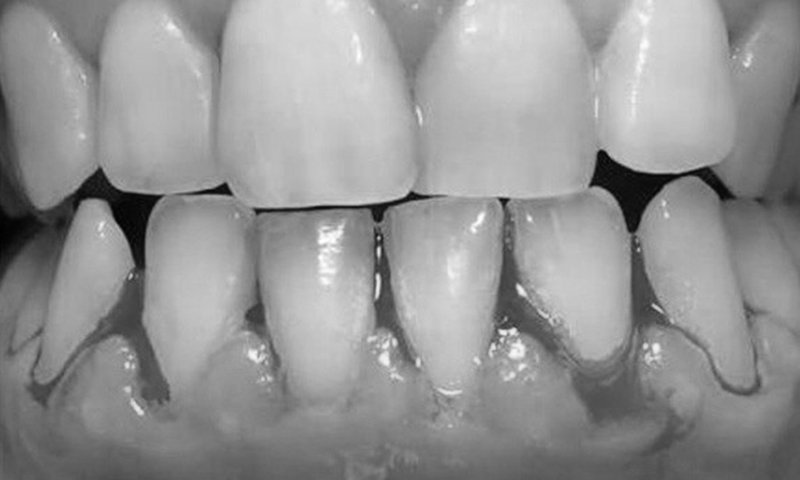

A gengivite e a periodontite, para facilitar, podem ser compreendidas como uma mesma doença, porém em estágios diferentes. A principal diferença é que na, periodontite, ocorre uma perda irreversível do osso que suporta as raízes dentárias. Além dos danos às gengivas e desconfortos como o sangramento gengival e inchaços frequentes, ambas podem ter consequências que vão muito além da cavidade oral.

A retração gengival já é um dos principais motivos para consultas ao dentista. Entre suas principais causas estão a periodontite e o trauma gengival por uso inadequado da escova dentária – este, fácil de ser resolvido através da adoção de escovas dentárias macias e novos hábitos de higienização oral.

O aparecimento de gengivas retraídas requer monitoramento por medição, algo simples e que pode ser realizado a cada consulta periódica para limpeza dos dentes. As funções deste procedimentos é verificar a velocidade de progressão da retração das gengivas e necessidade para adoção de tratamentos preventivos que podem incluir até mesmo a cirurgia plástica gengival para recobrimento de raiz dentária exposta – em casos mais severos, associada ao enxerto gengival.

O monitoramento da retração gengival é parte da consulta para limpeza dental.